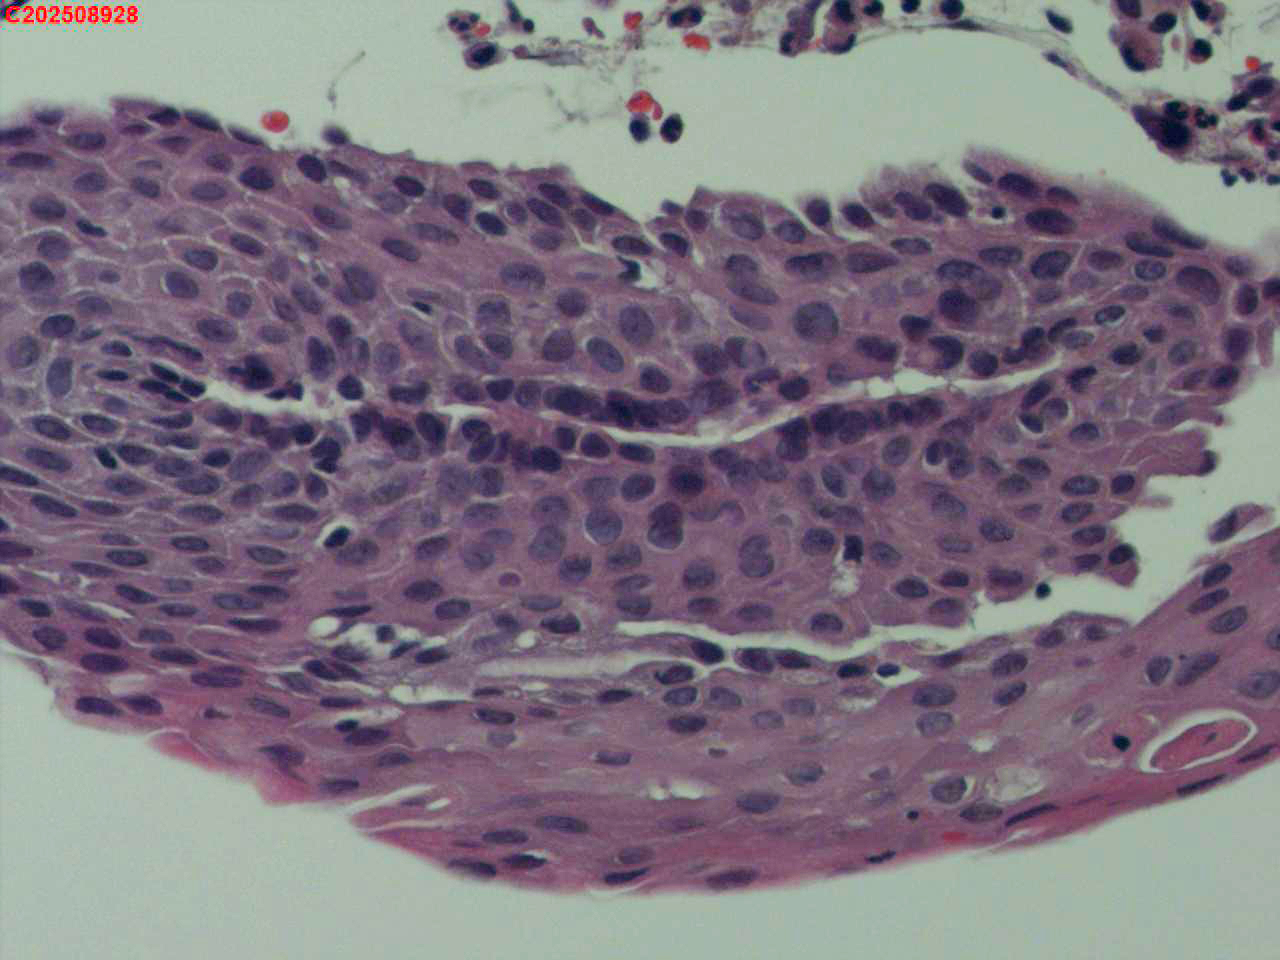

喉部右侧、声带下方咬检

喉室内右侧声带下方新生物。

考虑鳞癌

鳞癌,有微浸润